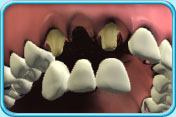

圖中所見是上排前牙,當中有一缺牙位置,其左右兩旁各有一顆已給預先處理的牙齒;此外,這些牙齒之下有一副由三顆假牙相連而成的牙橋,其大小及位置可配合套在前述已給處理的真牙上。